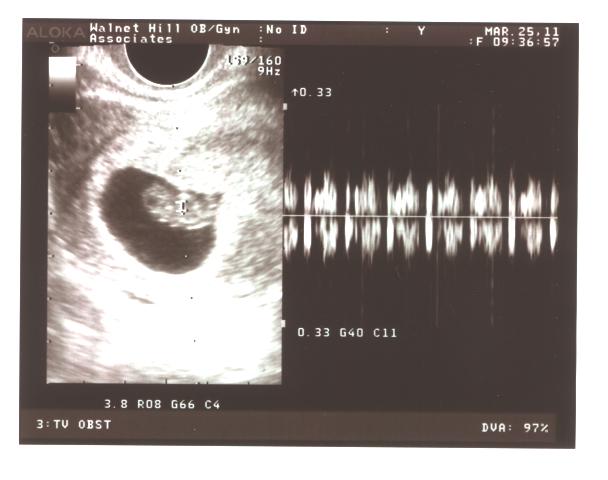

What else was I not expecting? To hear the baby's heart beat!!! Oh my gosh, I know it's so cliche to be all excited about hearing the whump-whump-whump on the ultrasound machine (and trust me, I've dopplered a crap ton of pulses on surgical patients in my time. It's just a freaking heart beat, right?), but it was a heart beat from a less than 2 centimeter little head, body, arms, and legs that is nesting somewhere between my hip bones this second! Me and Brandon made that! And you could SEE the heart beat on the ultrasound! (not so noticeable on the pictures, obviously, as they're not really flash images that move, ya know.)

Some state measuring 8w1d and another at 8w3d...but I'd say our due date is holding steady at beginning of November!

This one is when we got to hear the heartbeat! On the right is the heartbeat's signal.

See the perfect little baby?! (of course I'm freaking biased!)